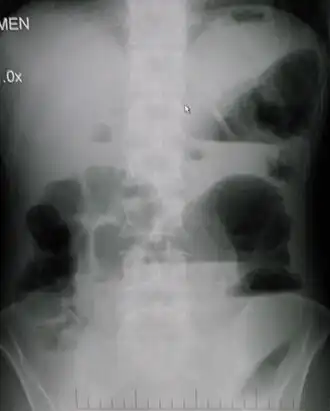

- Рентгенография брюшной полости

- определение газа и уровней жидкости в петлях кишок (чаши Клойбера)

- поперечная исчерченность кишки (симптом керкринговых складок)